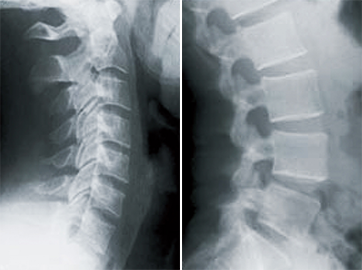

image

第2段階

• 椎間板スペースの減少

• 関節面や椎骨の変性

• 中度の可動域制限

• 神経組織の損傷